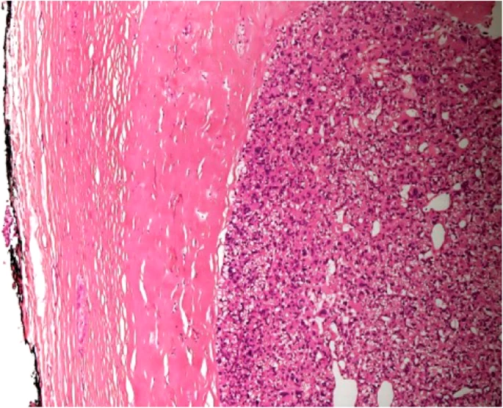

Thick capsule. A characteristic feature of both atypical parathyroid adenoma and parathyroid carcinoma (Courtesy Dr. V. Penopoulos)